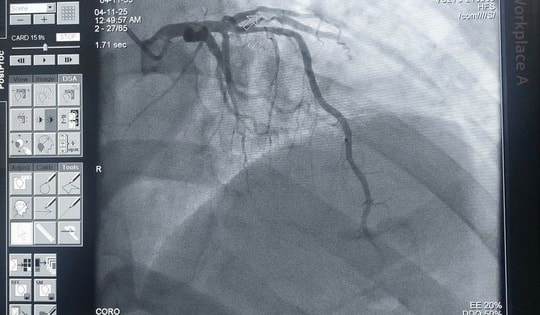

Cứu sống nam bệnh nhân bị nhồi máu cơ tim khi chơi đá bóng

Bệnh viện Đa khoa Ninh Thuận vừa cấp cứu thành công nam bệnh nhân 32 tuổi bị nhồi máu cơ tim khi đang chơi bóng đá.